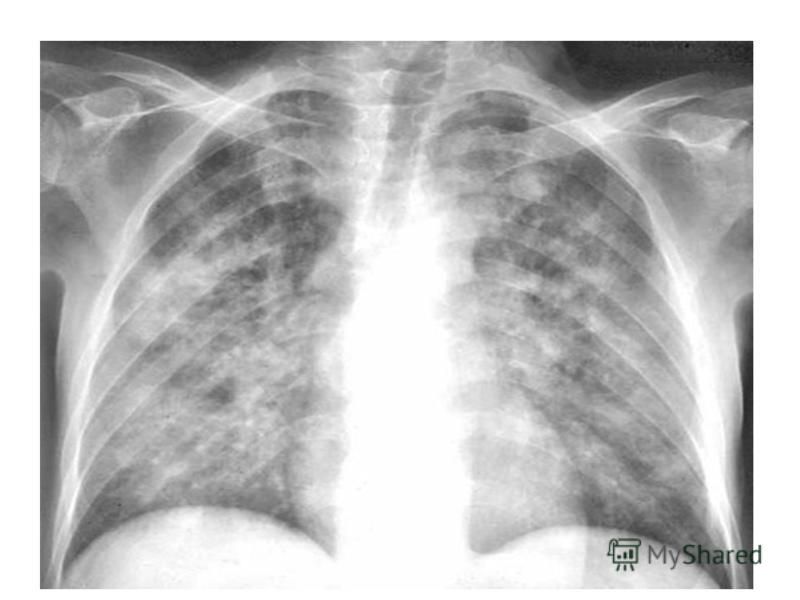

Рентгеновские снимки при пневмоцистной пневмонии